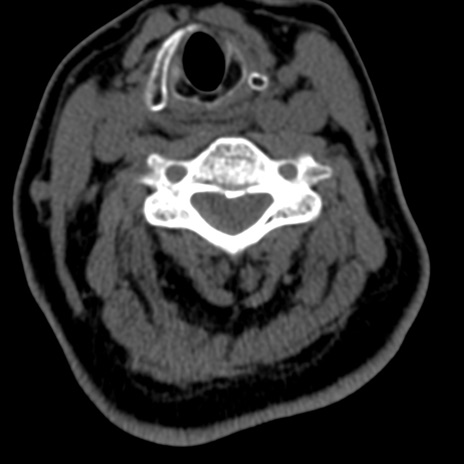

症例50 頚椎CT(横断像)

頚椎CT